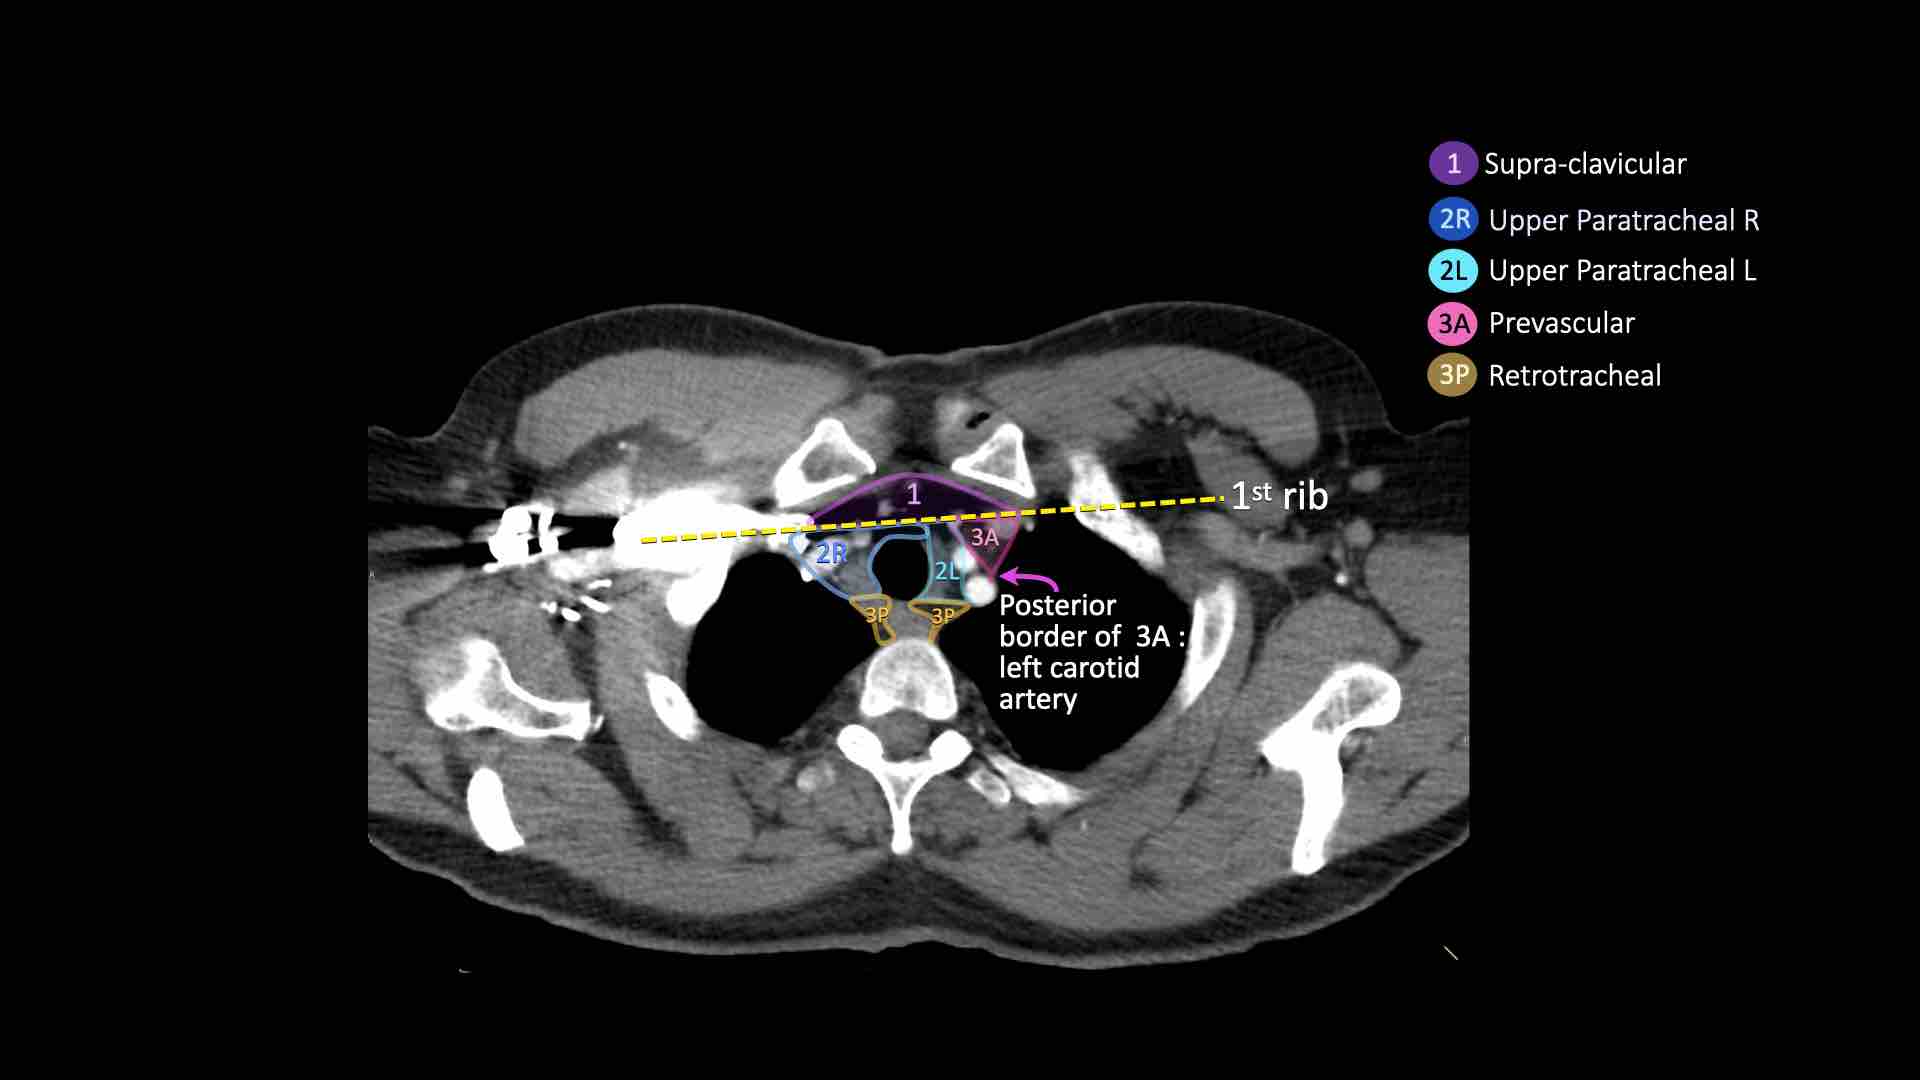

Giải phẫu CT cắt ngang

Nhấp vào hình ảnh để phóng to.

Sau đó cuộn qua các ảnh CT cắt ngang.

Hình ảnh do Bác sĩ Aurelia Fairise thuộc Viện Ung thư Lorraine tại Nancy cung cấp.

3. Hạch trước mạch máu và trước cột sống

Hạch nhóm 3 không nằm kề khí quản như hạch nhóm 2.

Chúng có thể là:

3A nằm phía trước các mạch máu, hoặc

3B nằm phía sau thực quản, vốn nằm ở vị trí trước cột sống.

Bên trái là hạch 3A nằm trong khoang trước mạch máu.

Lưu ý cũng có các hạch cạnh khí quản dưới bên phải, tức là hạch nhóm 4R.

- Cạnh khí quản trên: phía dưới xương đòn, bên phải nằm trên giao điểm của bờ dưới tĩnh mạch vô danh (tĩnh mạch tay đầu trái) với khí quản, bên trái nằm trên cung động mạch chủ

- Trước mạch máu và Sau khí quản: nằm trước các mạch máu (3A) hoặc trước cột sống (3P)

3A.Trước mạch máu

Các hạch này không tiếp giáp với khí quản như các hạch ở nhóm 2, mà nằm ở phía trước các mạch máu.

3P.Trước cột sống

Các hạch không tiếp giáp với khí quản như các hạch ở nhóm 2, mà nằm sau thực quản, tức là ở vị trí trước cột sống.